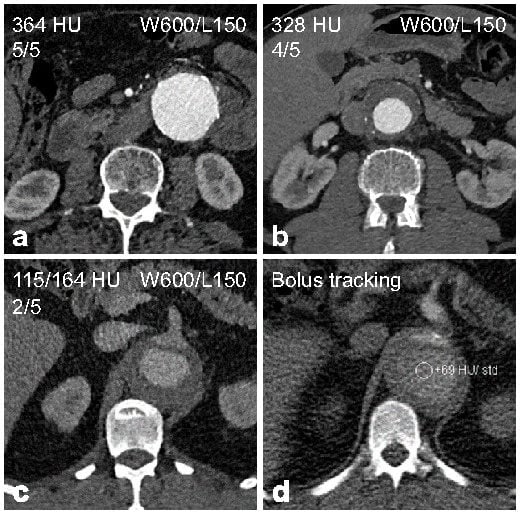

| Rating | Description |

| Excellent (5) | Aorta and iliac arteries with excellent enhancement and little noise. |

| Good (4) | Aorta and iliac arteries with good enhancement and little to moderate noise. |

| Moderate (3) | Aorta or iliac arteries partially with low to moderate enhancement and/or moderate to high noise. |

| Fair (2) | Aorta and iliac arteries completely with low enhancement and/or high noise. |

| Non-diagnostic (1) | Aorta or iliac arteries partially with insufficient enhancement and/or disruptive noise. |

| Rating | All Patients n = 161 | Group A (BMI < 30 kg/m2) n = 126 | Group B (BMI ≥ 30 kg/m2) n = 35 |

| Average * | 4.5 ± 0.6 | 4.6 ± 0.5 | 4.1 ± 0.9 |

| Excellent | 78 (48.4) | 69 (54.8) | 9 (25.7) |

| Good | 66 (41.0) | 49 (38.9) | 17 (48.6) |

| Moderate | 13 (8.1) | 8 (6.3) | 5 (14.3) |

| Fair | 3 (1.9) | 0 (0) | 3 (8.6) |

| Non-diagnostic | 1 (0.6) | 0 (0) | 1 (2.9) |